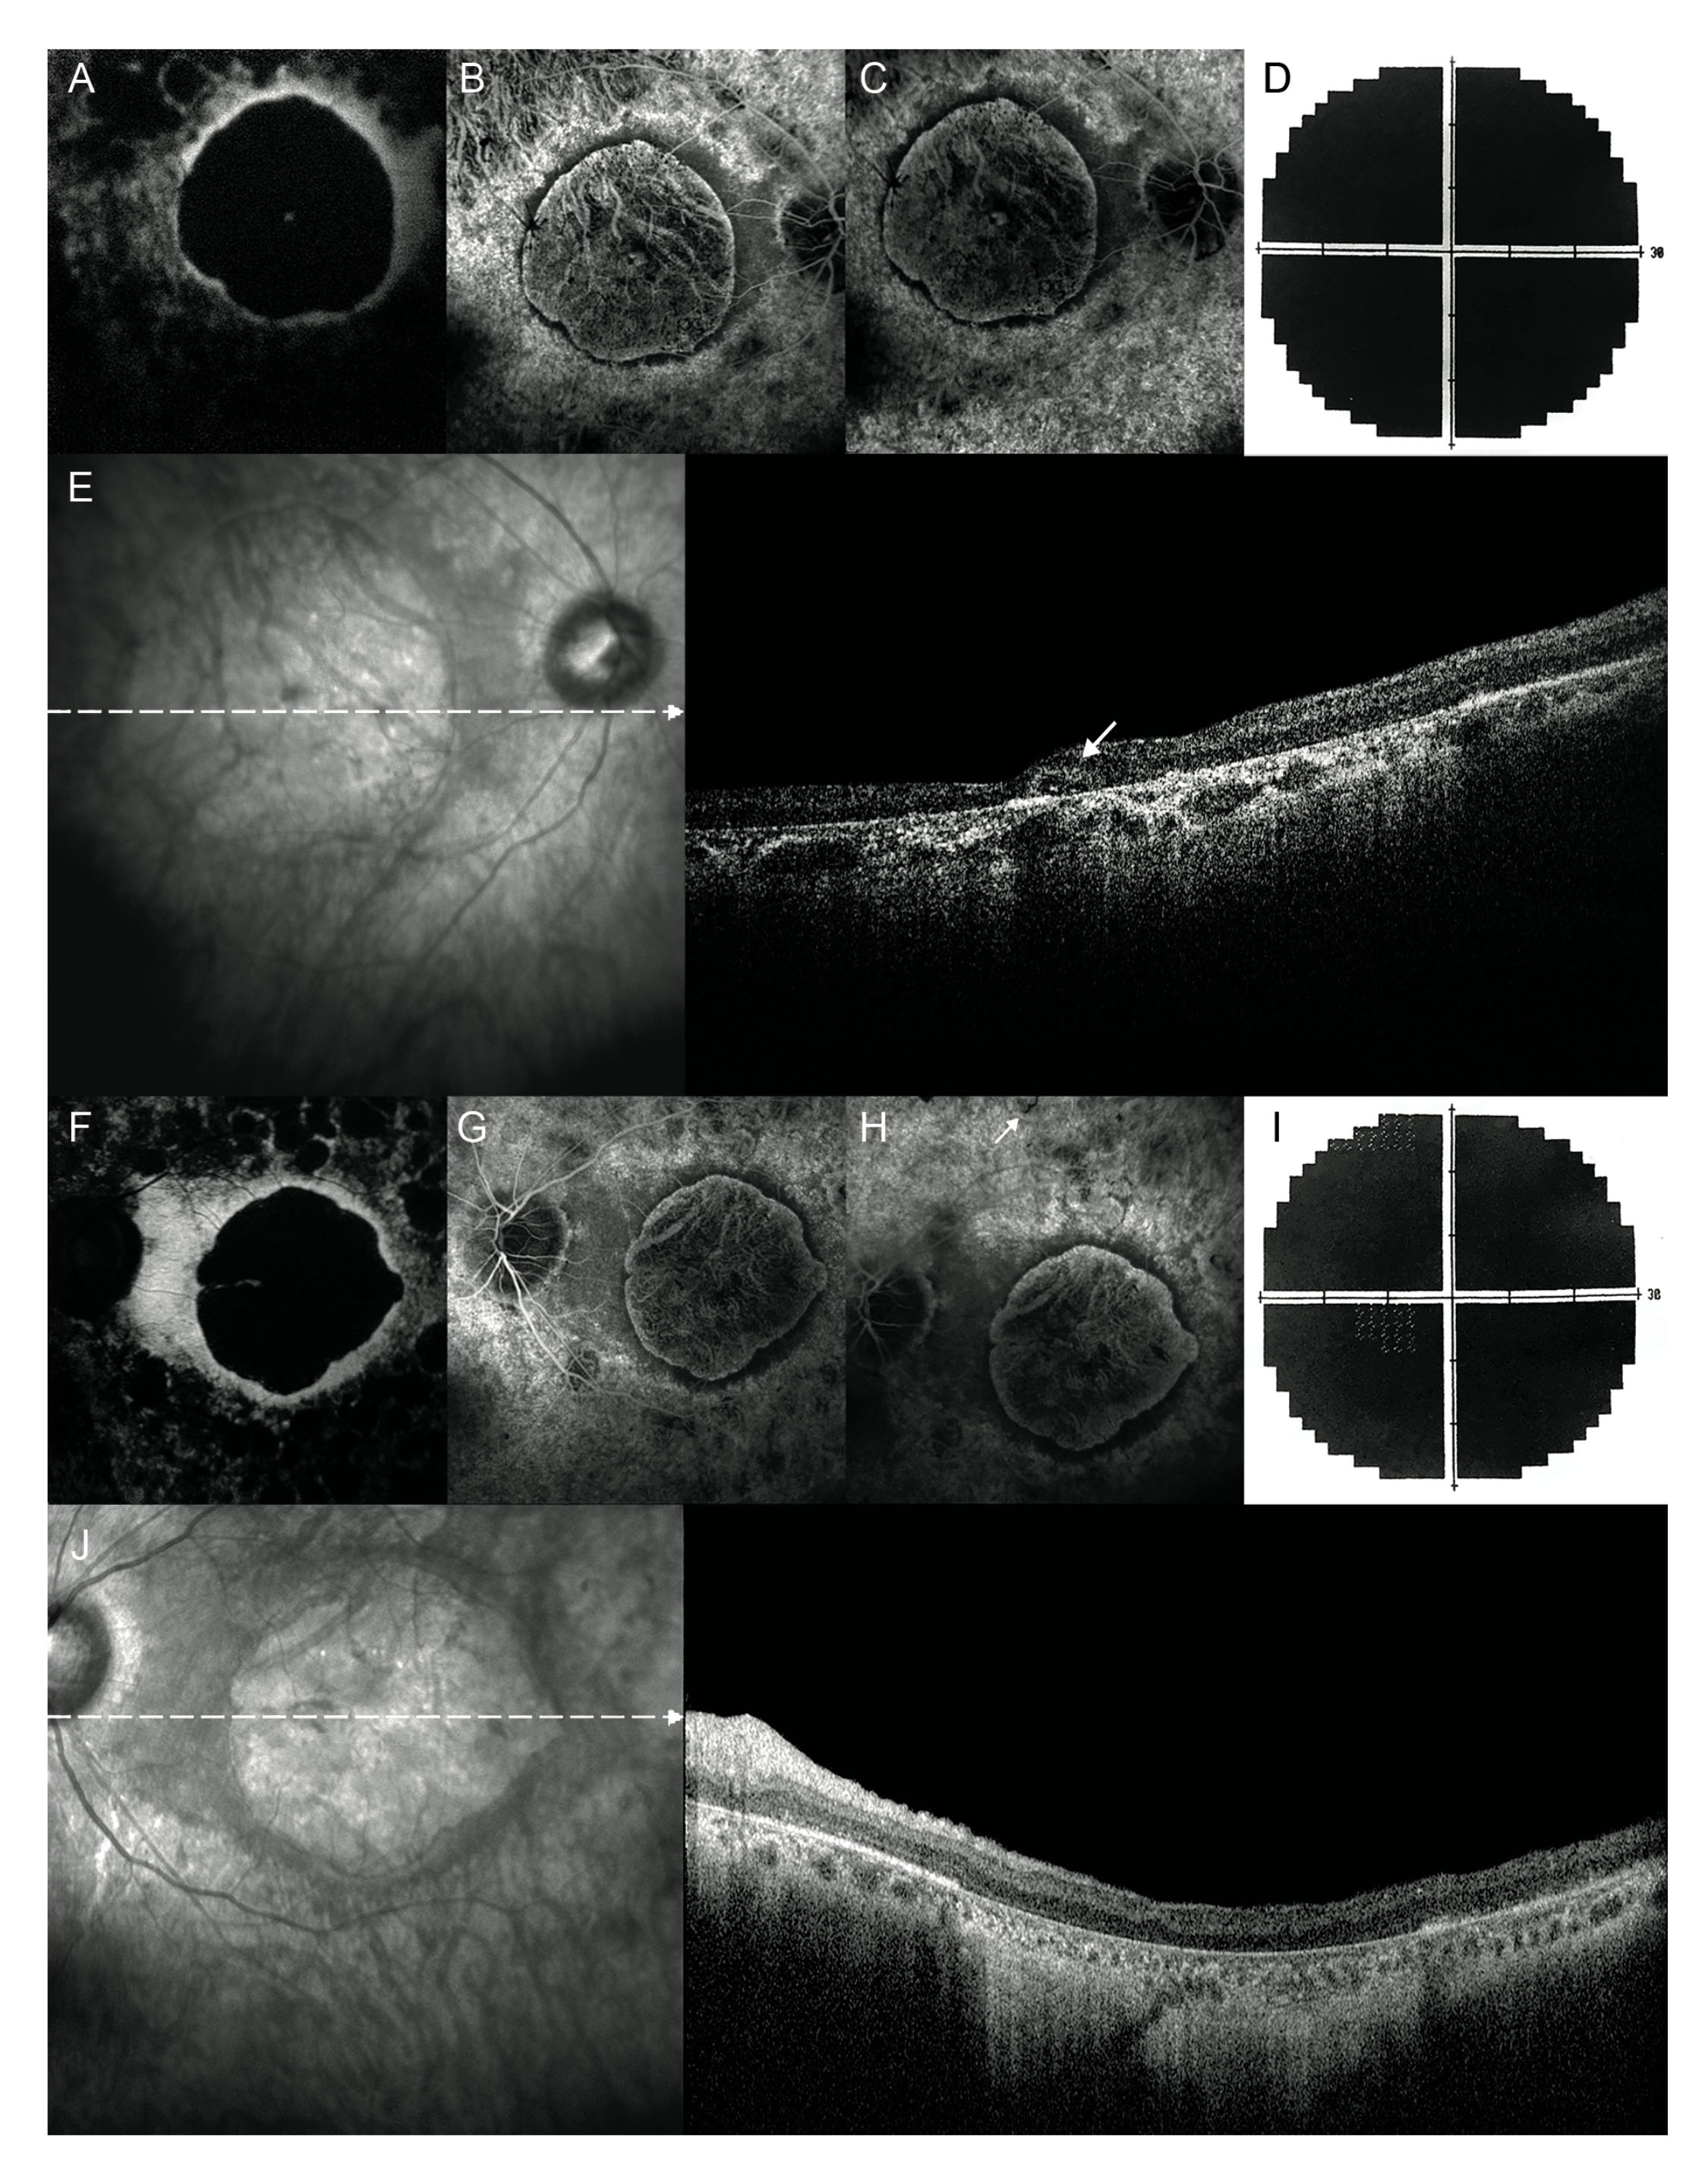

Figure 3. Fundus autofluorescence, fluorescein angiography, and visual fields, 20 years later. A, F: In both eyes, fundus autofluorescence shows a central round area of decreased autofluorescence corresponding to the area

of macular atrophy, surrounded by a ring of relatively increased autofluorescence. In the mid-peripheral retina, several roundish

areas of reduced autofluorescence, suggestive of patchy atrophy, can be seen. B, C, G, H: In both eyes, fluorescein angiography frames reveal a severe macular atrophy surrounded by a ring of preserved retinal pigment

epithelium. The mid-peripheral retina is extensively atrophic with some sparse pigmentary deposits (white arrow in H). D, I: Bilateral visual field extinction. E: In the right eye, simultaneous infrared and spectral domain optical coherence tomography show an ovoid tubular structure

with a partial hyperreflective border and hyporreflective material inside, suggestive of an outer retina tabulation (white

arrow) while (J) in the left eye reveal a severe retinal thinning secondary to the atrophy of the external retinal layers with backscattering.